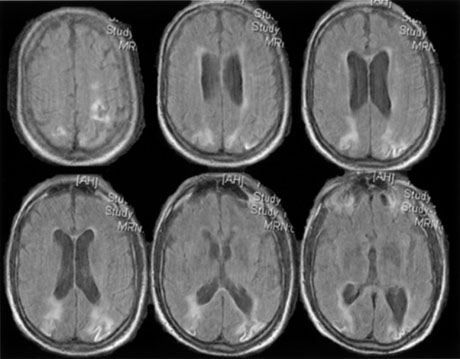

Fig. 15. Bilateral incomplete hemianopia. A 69-year-old man with decreased vision after prostate surgery. A. Fields show remaining central parafoveal vision with some sparing of inferior left quadrant. Note how the defect respects the vertical meridian. B. MRI shows bilateral medial occipital infarction, with sparing of the occipital poles, accounting for the macular-sparing bilaterally. (Courtesy of Dr. Lucia Vaina.)

Bilateral lesions of striate cortex are not rare. Focal midline lesions such as tumors or traumatic injury may affect both striate cortices concurrently, because the right and left striate cortices face each other on the medial occipital surface. The most common cause, however, is posterior circulation ischemia.57 This can affect both striate cortices either simultaneously or sequentially,57 because the right and left posterior cerebral arteries have a common origin from the basilar artery. Twenty-two percent of patients with a unilateral occipital infarction develop bilateral infarction over 3 years.58 Bilateral incomplete hemianopia is distinguished from bilateral optic nerve or ocular disease by the high congruity of the visual fields and step defects along the vertical meridian which indicate the hemifield nature of the visual loss (Fig. 15).57 Such steps are important to seek with a skilled perimetrist, but even so they can be difficult to demonstrate with bilateral hemiscotomata from occipital pole lesions.59 Bilateral quadrantanopias can occur,47,48 often in patients with prosopagnosia and achromatopsia for example, and may mimic the altitudinal defects of optic neuropathy.